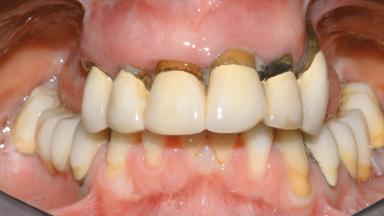

Conventional Loading of Eight Implants in the Maxilla and Final Restoration with a Full-Arch Gold-Ceramic FDP

A 35-year-old Caucasian female presenting with advanced periodontal disease involving both the maxillary and the mandibular dentition was referred for evaluation. The patient, a non-smoker in good general health, requested treatment for recurrent periodontal abscesses, tooth mobility, and discomfort during chewing, as well as restoration of her missing teeth with a fixed prosthesis to improve mastication and esthetics. All residual maxillary teeth exhibited plaque deposits, deep pockets, bleeding on probing, and class III mobility and were evaluated as hopeless. All residual mandibular teeth except tooth 37 could be maintained after periodontal therapy.

Periodontal Status History of periodontitis or genetic predisposition